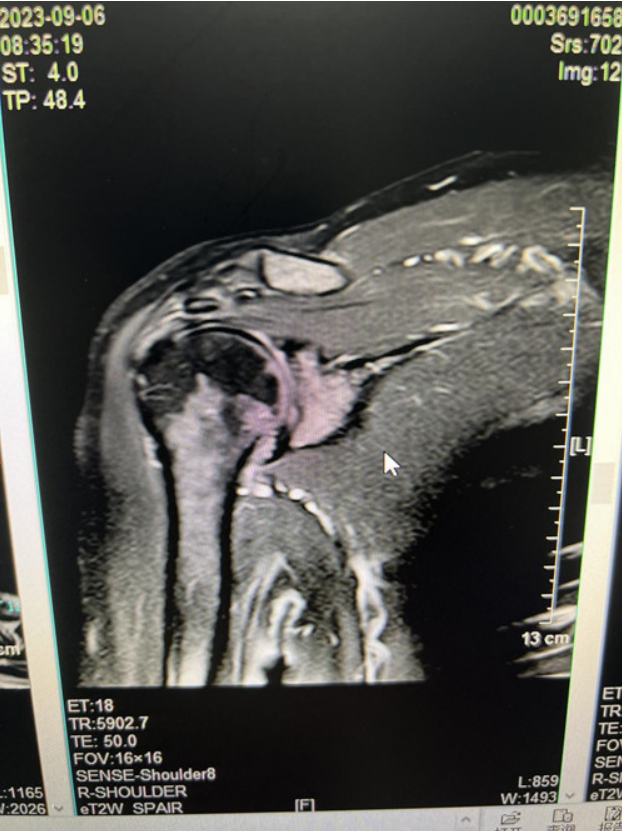

近半年来,我院康复医学科团队

为多位肩袖损伤的患者进行了

全面的康复治疗,

解决了患者的肩痛问题,

使患者关节功能及日常生活能力

得到很大改善。

患者情况